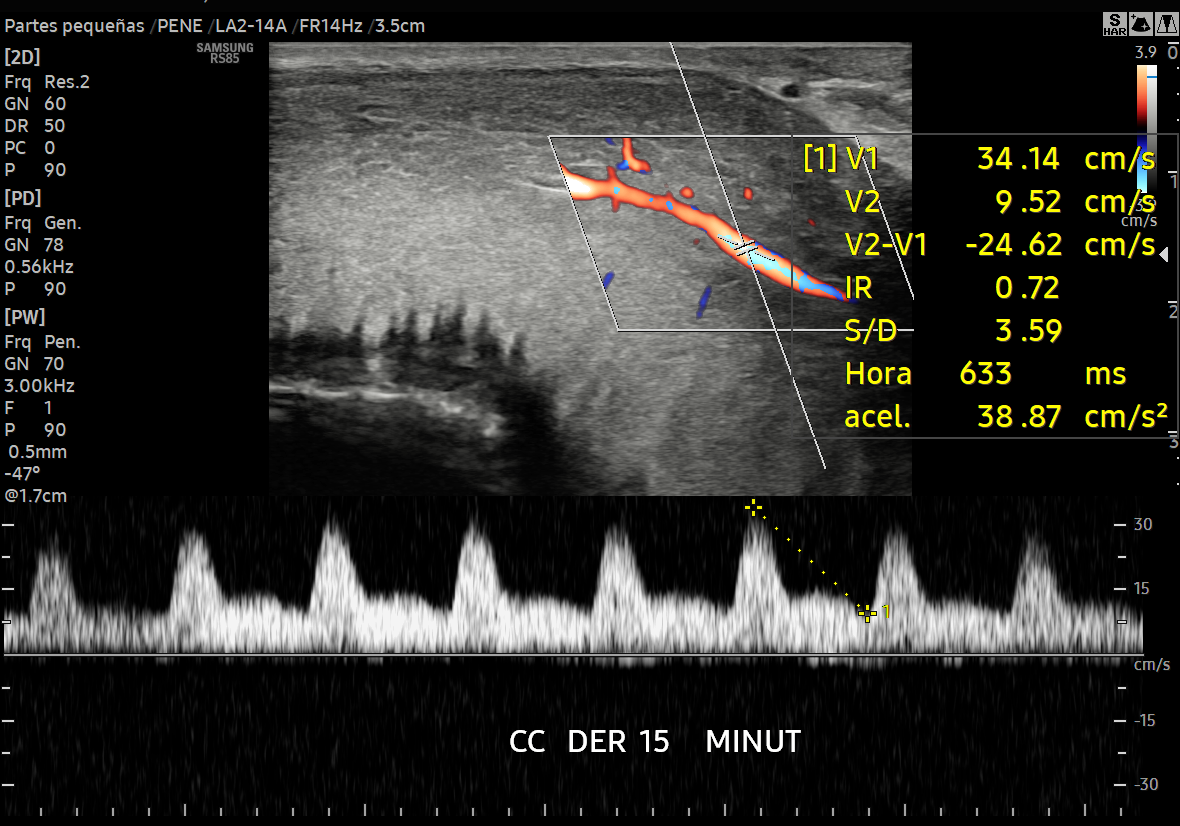

ECOGRAFÍAS ESPECIALIZADAS Elastografía de Hígado Cuantificación de Esteatosis Multiparamétrica de Hígado Elastografía de Tiroides Multiparamétrica de Tiroides Elastografía de Mama Multiparamétrica de Mama Doppler de Pene con sustancia Vasoactiva Multiparamétrica de Ganglios

ECOGRAFÍAS DE 2DA OPINIÓN Hígado Tiroides Mama Venoso Arterial Carotideo Partes Blandas Urológica - Pene Hígado Trasplantado Riñón Trasplantado